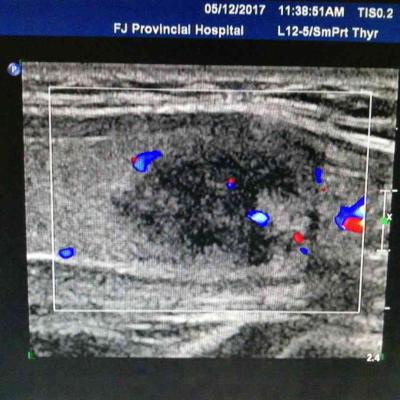

男性,40岁,70 Kg,175 cm, 风华正茂,事业正当时,并不嗜酒,却每日应酬不断,新近查肝功能异常,如下图1: 常规排除各种病毒性肝炎,自身免疫性肝炎,药物性肝病等可能,B超提示有脂肪肝,为进一步确定肝损伤程度,肝穿刺病理所见,肝小叶广泛肝细胞脂肪样变,大于50%,气球样变性,中性粒细胞浸润,窦周纤维化。为典型酒精性肝病。中度肝纤维化(S2)。 全球酒精性肝病患病率呈现持续增长趋势。我国尚缺乏酒精性肝病的全国性大规模流行病学调查资料,但地区性流行病学调查显示,我国饮酒人群数量和酒精性肝病的患病率有迅速上升趋势。华北地区流行病学调查显示,从上世纪80年代初到90年代初,嗜酒者在一般人群中的比例从0.21%升至14.3%;本世纪初,南方及中西部省份流行病学调查显示,饮酒人群增至30.9%~43.4%。 酒精性肝病占同期肝病住院患者的比例也在不断上升,从1991年的4.2%增至1996年的21.3%;来自解放军第三0二医院的研究报道,2002年至2013年十余年间,因酒精性肝病住院的患者比例上升了170%。由此可见,在我国,酒精所致的肝脏损害已经成为一个不可忽视的问题。 酒精滥用和依赖显著增加了酒精性肝硬化的发生风险,其中在40~59岁人群最为显著。此前曾有报道,长期的每天饮酒,尤其是饮白酒或啤酒,更易引起酒精性肝硬化。 一份回顾性研究结果显示,早期/代偿期酒精性肝病患者的5年肝病相关死亡率为13%,而失代偿期患者则高达43%;早期/代偿期酒精性肝病患者的长期预后受到肝纤维化分期的影响,其中严重纤维化(F3/4)对10年死亡率有重大影响;对于失代偿期酒精性肝病患者,临床特征(性别:女性)、肝衰竭的生物化学指标(胆红素、国际标准化比值)、组织学特征可以预测患者的长期生存率;随访期间,无论代偿期还是失代偿期酒精性肝病患者,戒酒都是生存率的重要预测指标。 也有研究报道,胆红素淤积的出现及其程度、巨型线粒体缺失、多形核白细胞浸润程度与酒精性肝炎患者的死亡率显著相关;酒精性肝炎组织学评分对于预测糖皮质激素的疗效和死亡率具有很高的准确性。 酒精性肝病相关恶性肿瘤不容忽视。来自日本的一项多中心研究结果显示,和非酒精性脂肪肝相比,酒精性肝病导致的肝癌的患者更年轻,肝纤维化水平更高,芬兰的一项包括1873例酒精性肝病患者的调查结果显示,酒精性肝病患者的恶性肿瘤发生率显著高于对照人群;其中重症酒精性肝病患者的肝细胞肝癌、上消化道癌症、胰腺癌等恶性肿瘤发病风险显著升高;该研究还指出,所调查的酒精性肝病患者当中,未发现任何一种恶性肿瘤的发病风险是降低的。